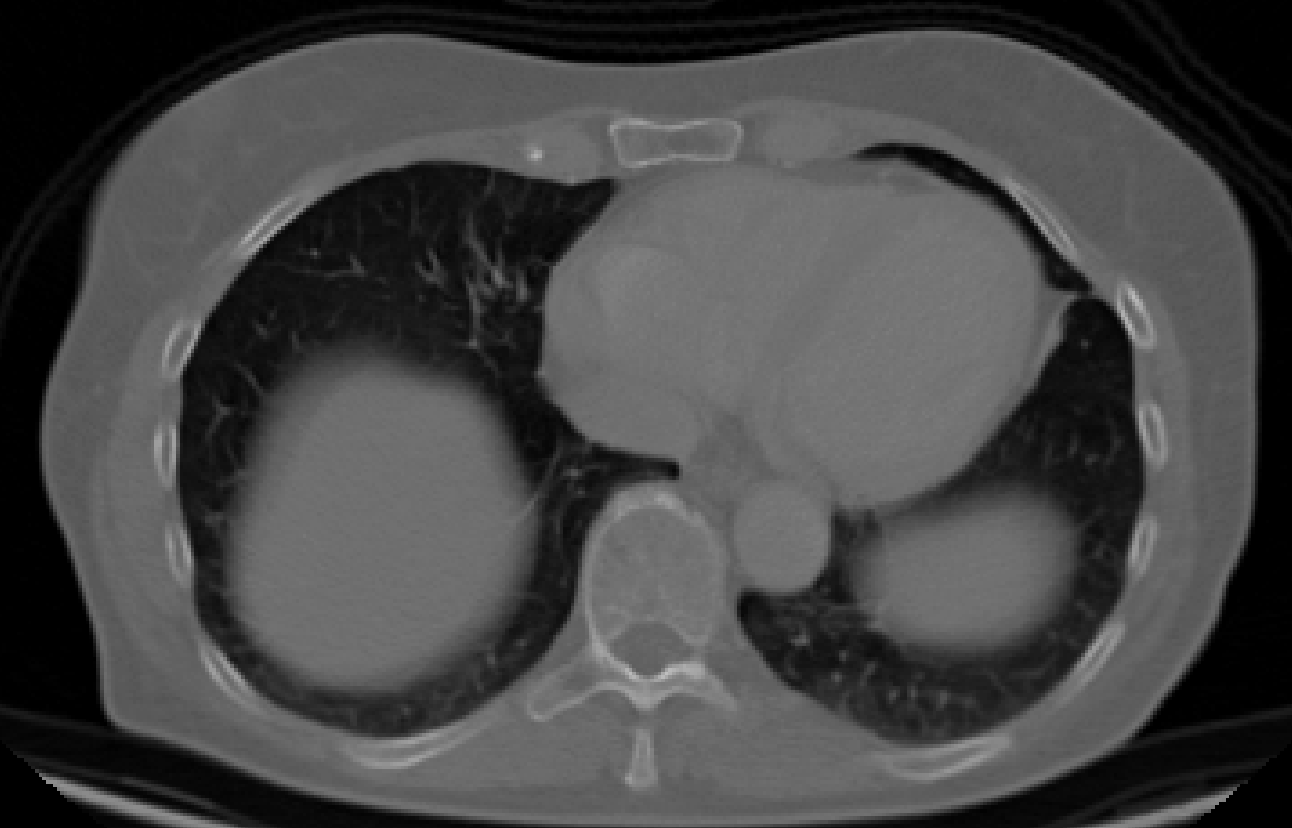

Welcome to our comprehensive cardiology annotation services. Our team of experienced medical professionals and advanced technology combine to provide accurate and detailed annotations for cardiology imaging data. From EKGs to echocardiograms, we offer precise and reliable annotations to support research, diagnosis, and treatment planning. Whether you're in need of precise measurements, feature detection, or anomaly identification, our services are tailored to meet your specific needs. Trust us to deliver high-quality, efficient, and insightful annotations for your cardiology data.